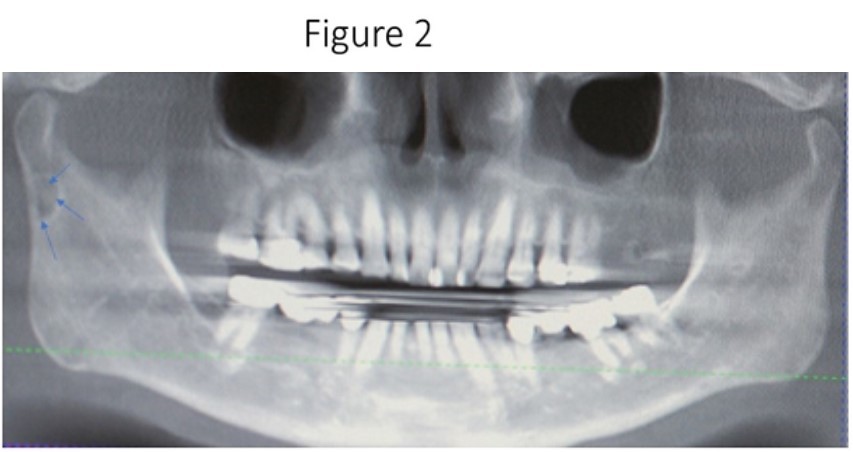

Maxillofacial examination was unremarkable. No facial swelling, masses or asymmetry was observed. The TMJ examination was normal. No pain or tenderness to digital palpation was observed in the right preauricular region. Oral examination of the patient was unremarkable. No trismus was observed as the maximal interincisive opening was greater than 40.0mm. No anterior or posterior open bite was observed. Imagining studies to rule-out intraosseous neoplastic lesions and arrive at a definitive diagnosis consisted of a panoramic radiograph and cone beam CT scan (120 kVp, 5 mA, 7.4 sec). Panoramic radiograph revealed a unilocular, well-circumscribed radiolucency in the right subcondyalar region of the mandible that was close to the posterior border of the condylar neck (Figure 2). Cone beam CT scan (i-CAT FLX, Imaging Sciences, Hatfield, PA) imaging revealed a well-defined unilocular, elliptical shaped radiolucent lesion on the medial surface of the right subcondylar neck of the mandible (Figure 3, Figure 4, Figure 5). The elliptical shaped unilocular lesion involved almost the entire horizontal dimension of the subcondylar neck (Figure 4). Figure 5 shows the three-dimensional CT scan reconstruction (i-CAT FLX, Imaging Sciences, Hatfield, PA) of the medial defect in the subcondylar region of the mandible. Based on knowledge of clinical head and neck anatomy and imaging studies, no treatment was indicated as the diagnosis was consistent with a variant of a Stafne bone cavity of the right subcondylar neck near the parotid gland and not a pathological condition. The patient was informed about the risk of condylar neck fracture due to the critical size of the SBC.

Figure 4.Cone beam CT TMJ sagittal views illustrate osseous defect on medial cortex. Note the thinness of the cortex that places the patient at risk for fracture of the condylar neck.

Cone beam CT TMJ sagittal views illustrate osseous defect on medial cortex. Note the thinness of the cortex that places the patient at risk for fracture of the condylar neck.